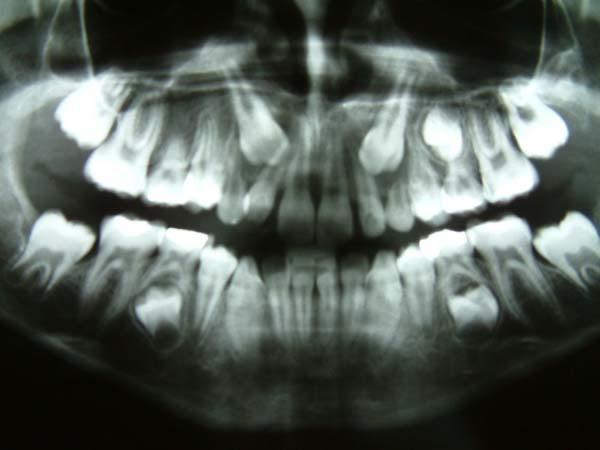

Στα 7 χρόνια του παιδιού εξετάζουμε με πανοραμική ακτινογραφία τη θέση των μονίμων άνω κυνοδόντων στο οστό και αναλόγως πράττουμε.

Γενετικώς ελλείποντα δόντια (ο άνω αριστερός πλάγιος, ο άνω δεξιός 2ος προγόμφιος, οι κάτω δεύτεροι προγόμφιοι αμφοτερόπλευρα.)